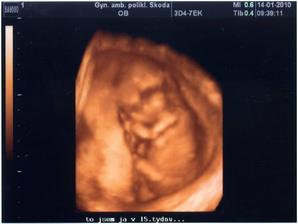

14.01.2010 15t + 4 máme 8,36cm a vše je v pořádku,už jsou nám vidět i kořínky na zoubky,prý vypadáme jak krokodýl 🙂) za týden výsledky krevních testů,snad bude vše ok...( o týden později - výsledky dopadli výborně a nemusíme na odběr plodové vody)